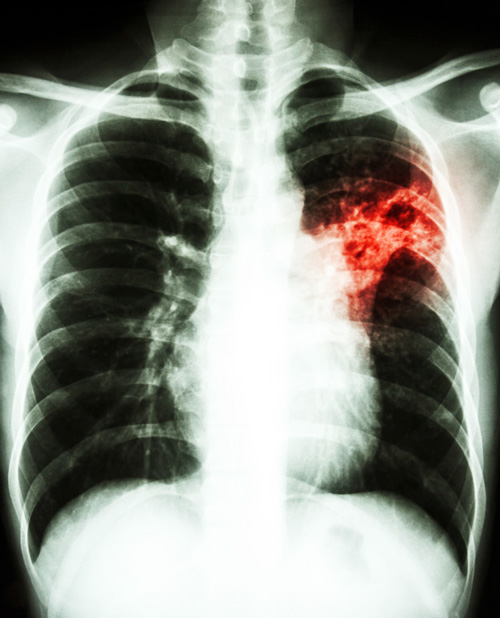

TB XraySupport pédagogique sur l'imagerie de la tuberculose

Nous avons le plaisir de vous présenter ce support pédagogique sur l'imagerie de la tuberculose développé par Soutien Pneumologique International (SPI), et de le partager avec la communauté pneumologique francophone et internationale.

Ce module de formation en ligne a été développé grâce aux généreuses contributions et le soutien d'un grand nombre de grandes sociétés et des ONG , dont Soutien pneumologique international (SPI). Il est accessibe via le site de la Société internationale de radiologie et la Commission internationale d'enseignement en radiologie (ICRE), à travers le projet Global Outreach Education (GO ED) à cette adresse.

A travers cette annonce et la coincidence avec la journée mondiale de la tuberculose, compte tenu de l'importance de la radiologie et de l'imagerie dans cette campagne de santé publique mondiale, nous espérons que cet outil précieux améliorera les connaissances en radiologie, le diagnostic et contribuera à l'éradication de cette maladie mortelle.